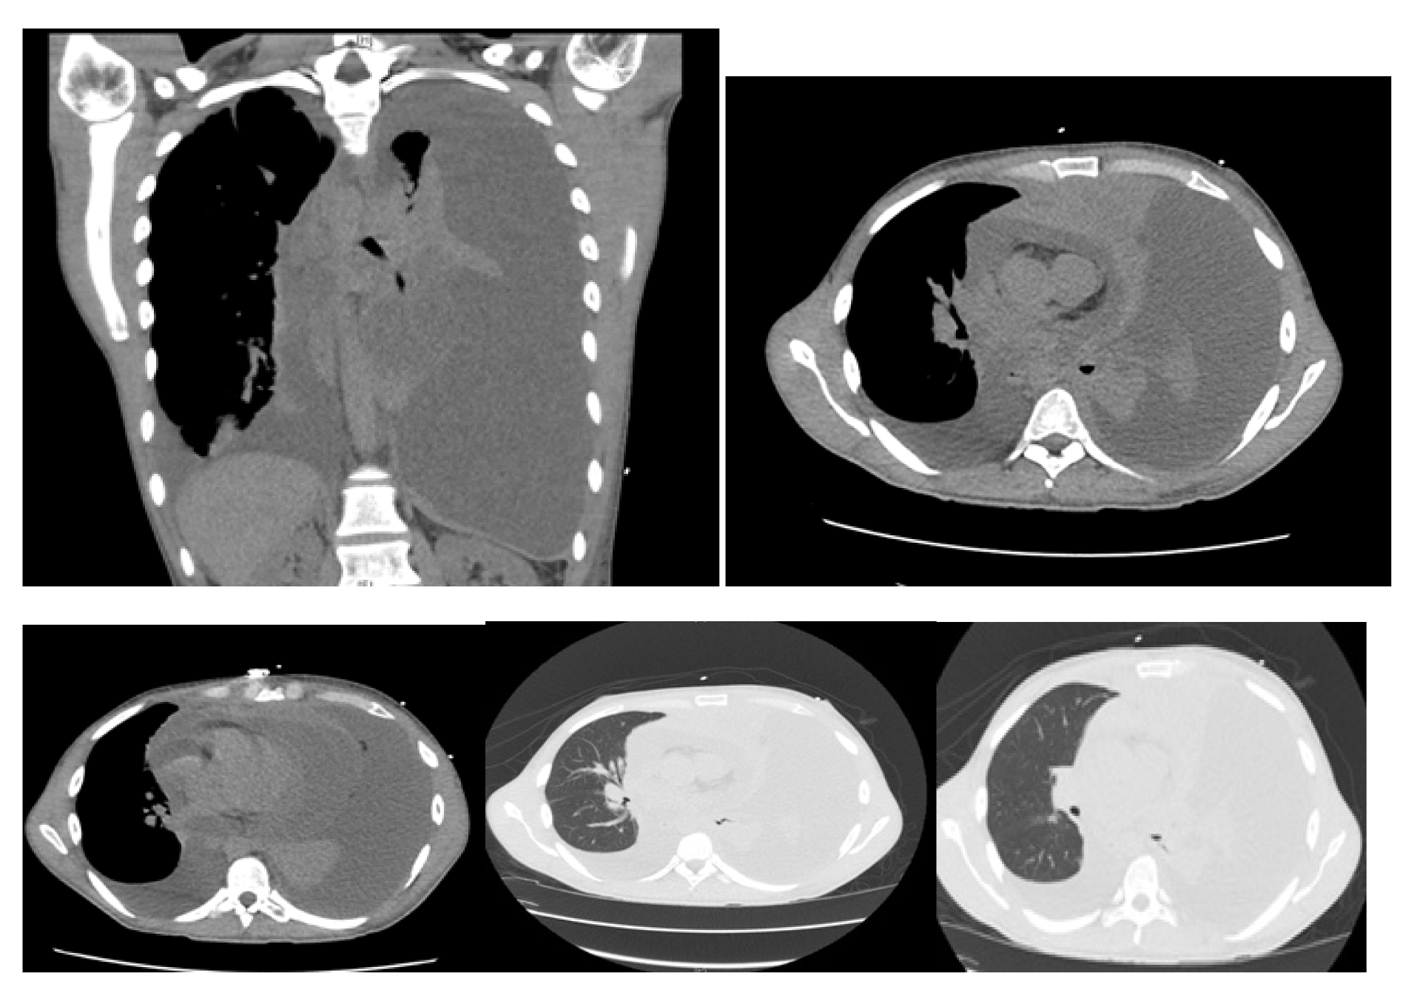

Computer tomography of the chest revealed: massive left pleural effusion with left lung atelectasis and shift of mediastinum from left to right, moderate right pleural effusion, massive pericardial effusion and a mass arising in the anterior mediastinum (Fig. 2).

![]() Click for large image | Figure 2. Computer tomography of the chest showing massive left pleural effusion, moderate right pleural effusion, massive pericardial effusion and a mass arising in the anterosuperior mediastinum. |